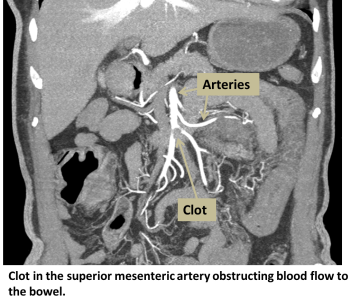

The blood supply to the gastrointestinal tract comes from three branches of the aorta: the celiac artery, the superior mesenteric artery, and the inferior mesenteric artery. Because there is overlap between the areas that these arteries supply, the arteries can try to compensate for blockages in other areas. However, uncompensated areas will suffer more damage from decreased blood flow.

If flow is being blocked because a clot has become lodged in an artery the approach is slightly different. Accessing the area of concern is achieved with a series of wires and tubes under x-ray guidance as described above. Once the area of concern is reached a special catheter can be placed in the clot and clot-busting medication can be delivered to help break up the clot.